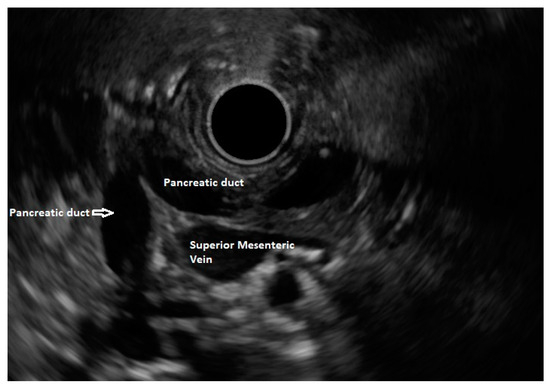

5. Pancreas Divisum

6. Endoscopic Ultrasound Features of Pancreas Divisum: Radial and Linear EUS